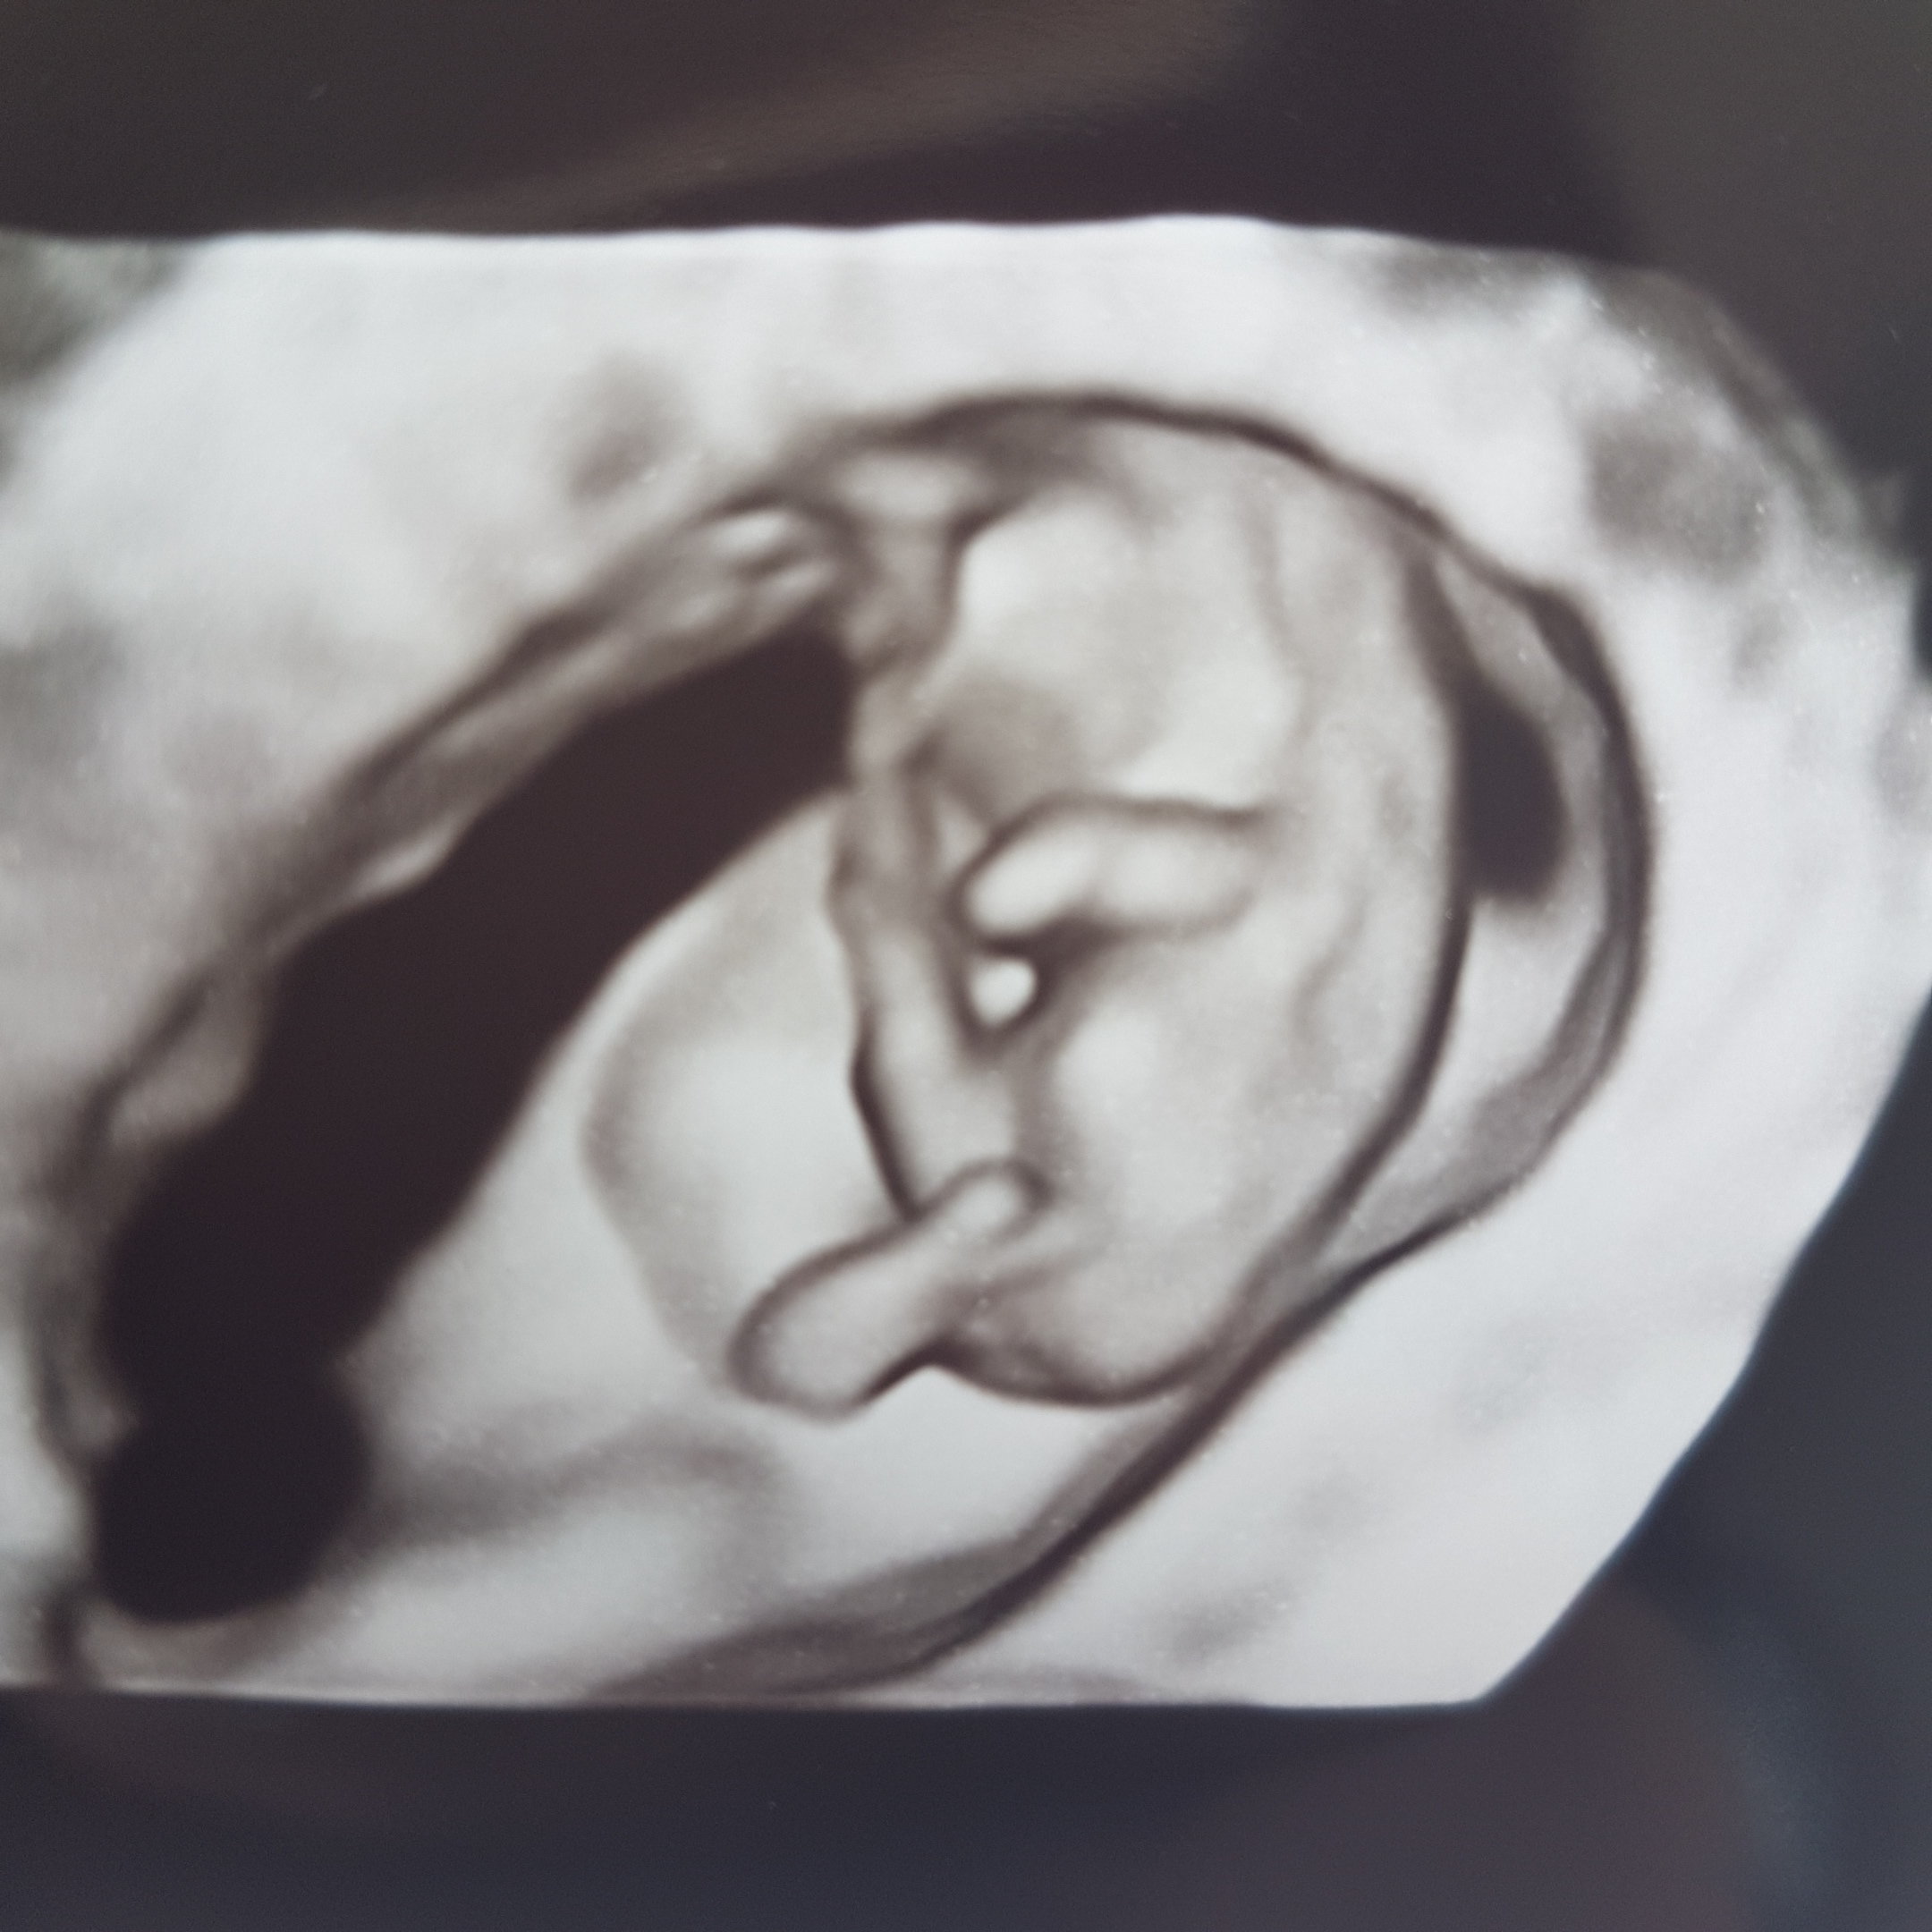

Już jestem. A więc jest wszystko dobrze,słyszałam serduszko. Aż się poplakalam. Widziałam jak się rusza. Moje maleństwo ma 3cm z om 10t1d z usg 10t0d 20170516_121935.jpg

Jestem taka szczęśliwa. Na zdjęciu widać lewą rączkę i nozke.